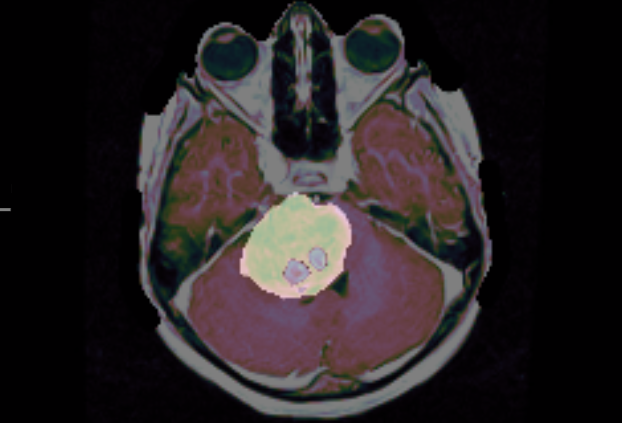

These results demonstrate great performance across all critical tumor cystic component (CC), peritumoral edema (ED), enhancing tumor (ET), non-enhancing tumor (NET), tumor core (TC), and whole tumor (WT). In Fig. 8, we present a representative example in which our model delivers highly accurate lesion segmentation, clearly illustrating its precise predictive capabilities.

Refer to caption

(a) Sagittal of case 381.

(b) Coronal of case 381.

(c) Axial of case 381.

Figure 8: BraTS_PED_00381

ET: 0.9575 NET: 0.9722 TC: 0.9749 WT: 0.9749